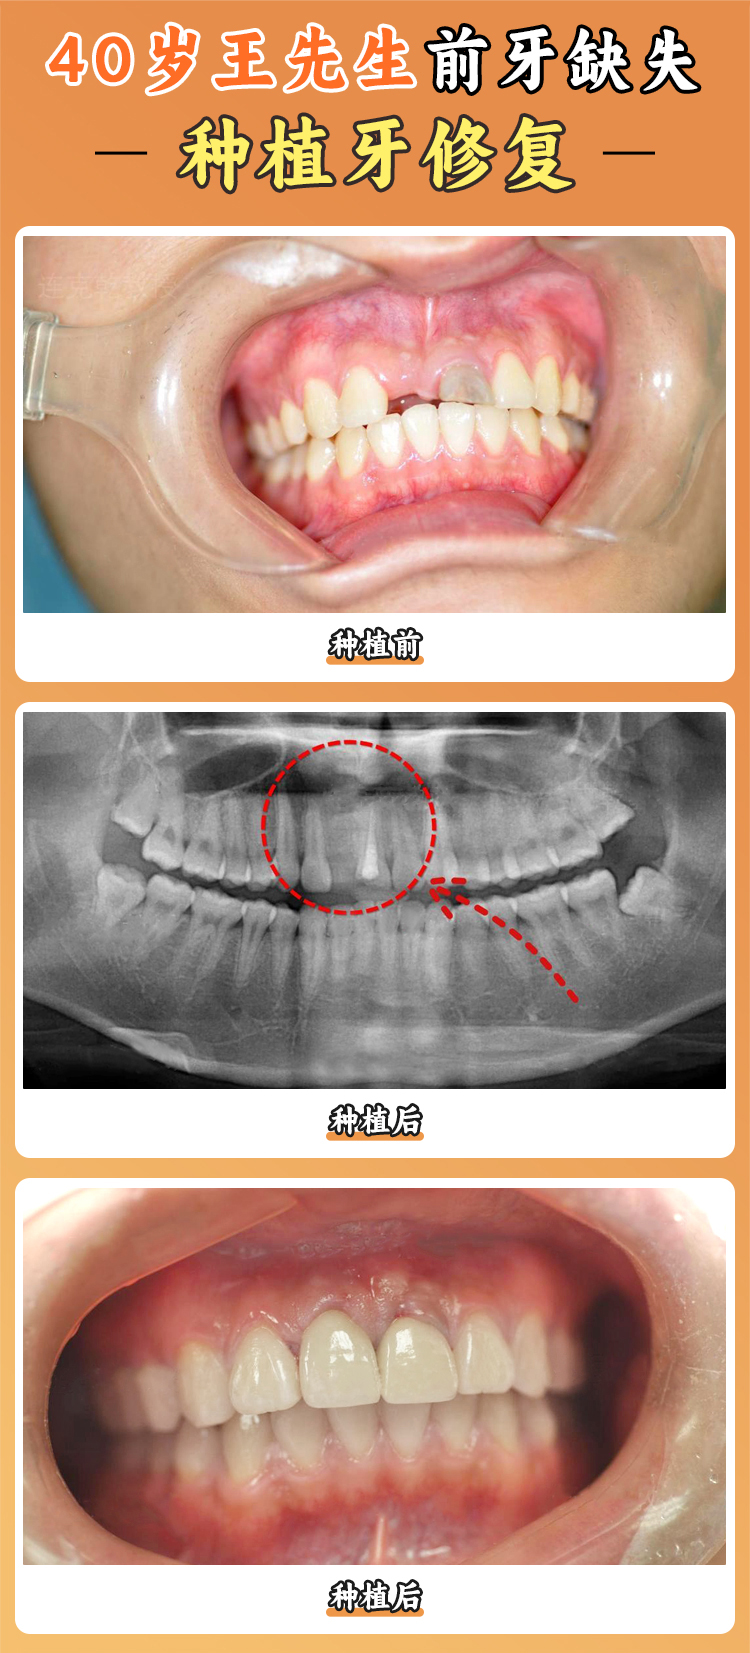

上海瑞伢美口腔提供齊全的口腔診療服務(wù),其中多個(gè)特色項(xiàng)目受到患者好評(píng)。數(shù)字化種植牙采用精良的3D導(dǎo)板種植技術(shù),通過(guò)CBCT精細(xì)掃描,計(jì)算機(jī)輔助設(shè)計(jì)種植方案,實(shí)現(xiàn)微創(chuàng)、精細(xì)、快速的種植牙手術(shù)。特別適合單顆牙缺失、多顆牙缺失甚至全口無(wú)牙的患者。這種技術(shù)可以將誤差控制在0.1毫米內(nèi),大大提高了種植牙的成功幾率。劉先生是全口牙缺失患者,在上海瑞伢美口腔接受了數(shù)字化種植牙手術(shù),術(shù)后修復(fù)快,種植牙的成效也非常好,現(xiàn)在他又能正常享受美食了。